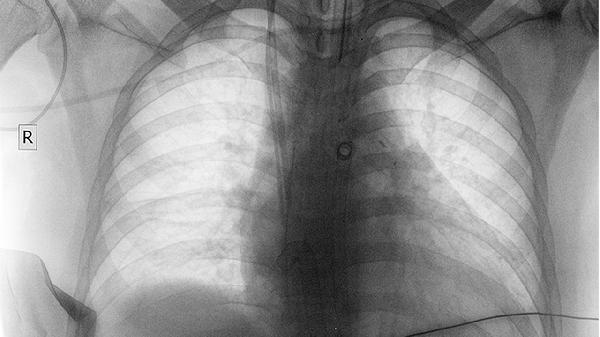

手术治疗中央型肺癌主要有三种方式。肺叶切除术是最常见的手术方式,适用于肿瘤局限于一个肺叶的患者。全肺切除术适用于肿瘤范围较大或侵犯主支气管的患者,但术后患者肺功能受损较多。袖状切除术是一种保留肺组织的手术方式,适用于肿瘤位于主支气管的患者,术后患者生活质量较高。